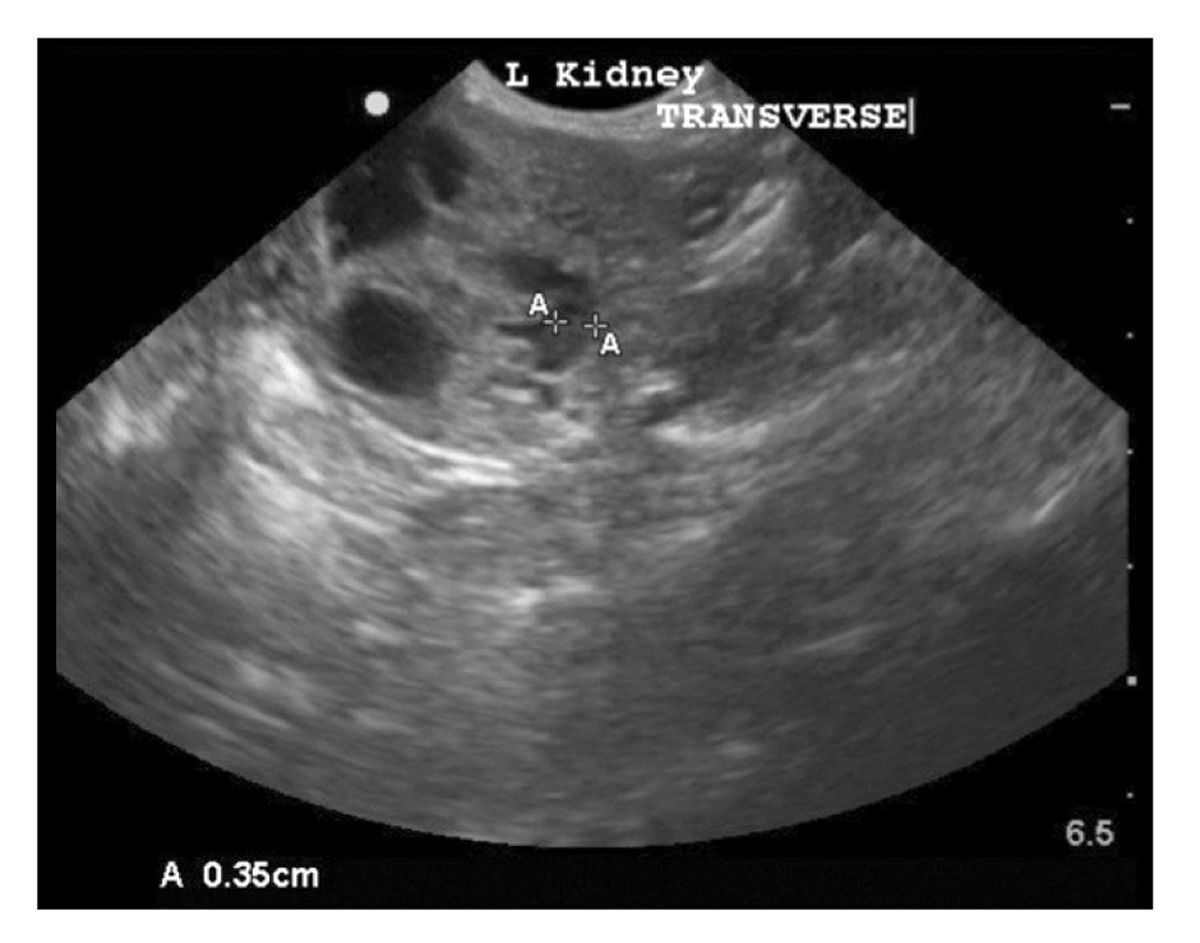

The second tip to correctly identify pericardial versus pleural effusions on ultrasound or echocardiography is to practice and get multiple windows. Abdominal ultrasounds were performed in 70 cats with pleural effusion and revealed concurrent abdominal effusion in 59 of these cats. Check out this video.

Its normal to see the spine behind the liver or the kidney but if you continue to see it up behind the thoracic space in back. Both computed tomography CT and ultrasound US can be used to differentiate ascites from pleural effusion. The most commonly diagnosed cause of pleural effusion in cats is chylothorax.

Ultrasonography Of Peritoneal And Retroperitoneal Spaces And Abdominal Lymph Nodes Today S Veterinary Practice